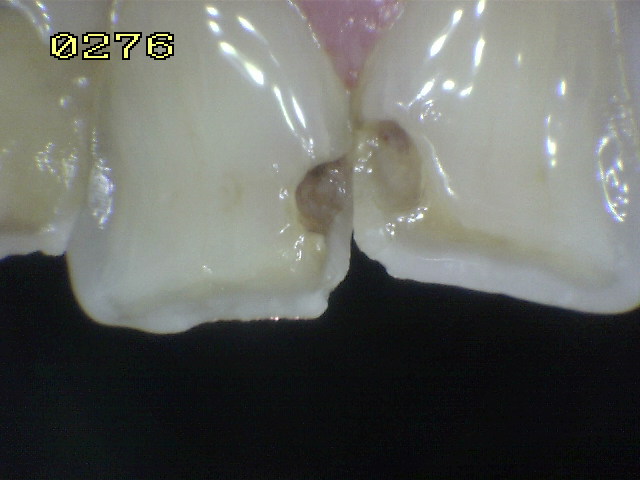

Árbol para el  diagnóstico de caries de esmalte y dentina

Código 6

Código 5

Código 4

Código 3

Código 2

Código 1

Código 0

Resumen del árbol diagnóstico para caries de esmalte y dentina